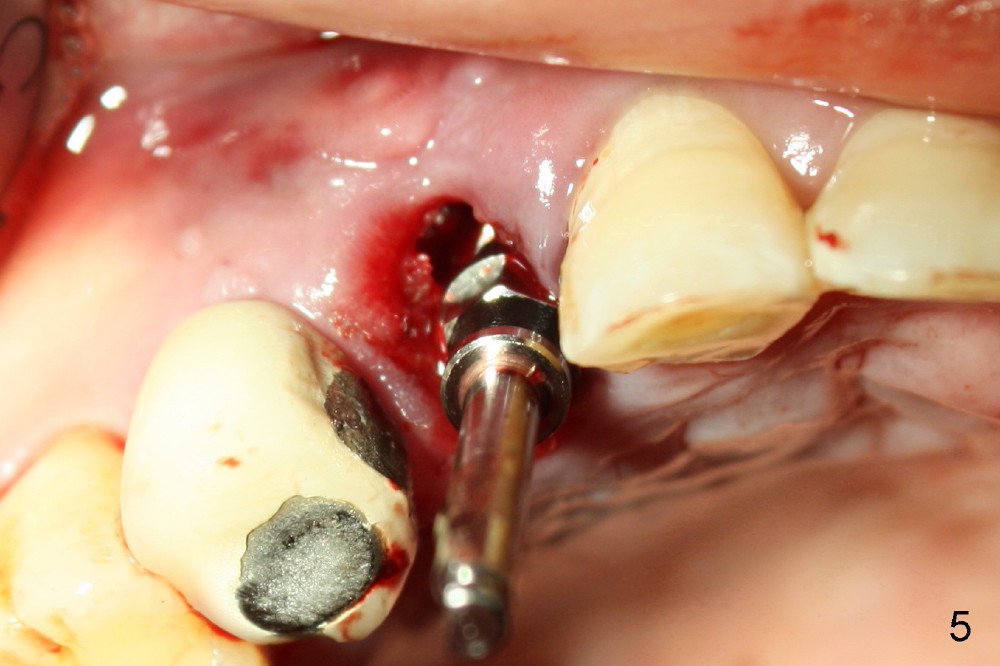

In spite of large periapical radiolucency (Fig.1 *), osteotomy is easier than expected. Use 2 mm pilot drill, 2.5-3.5 mm reamers from 14 mm (bottom of the socket) to 17 mm (sinus floor). The initial point for osteotomy at the bottom of the socket is easy to establish, because it is flat. By the time 5x20 mm tap is inserted, it is palatal (Fig.5). It is mandatory because the buccal plate has been perforated. The tap has to be inserted deeper (from 17 mm to 20 mm, Fig.6) to achieve stability. Insertion torque of 5x20 mm implant (Fig.7 I) is > 60 Ncm. The implant remains palatal so that there is space for bone graft (Fig.8 *). But the bone graft is a little over packed; there is no room to place collagen dressing. The latter will be dislodged and bone graft will be lost if perio dressing is loose prematurely. The perio dressing may have to be re-applied. Depth of bone graft is deemed sufficient if the implant threads are covered. Maximum will be on the rough surface. Physiologically, bone does not extend to the gingival margin.